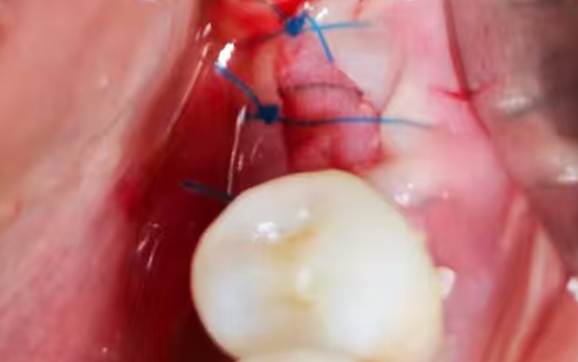

Suture completion post-implantation